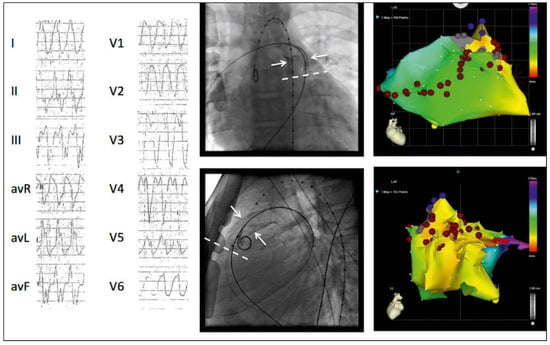

Ventricular Arrhythmias in Congenital Heart Disease: How Can the Electrophysiologist Help?

by Dipen Shah

Cardiovasc. Med. 2017, 20(2), 27; https://doi.org/10.4414/cvm.2017.00459 - 15 Feb 2017

Cited by 2 | Viewed by 72

Patients with congenital heart disease often have ventricular hypertrophy, dilatation and/or fibrosis as part or a direct consequence of their malformation. Moreover, they often have ventricular scars and/or patches and develop secondary haemodynamic overload or valvular abnormalities as a consequence of reparative surgery/interventions [...] Read more.

Patients with congenital heart disease often have ventricular hypertrophy, dilatation and/or fibrosis as part or a direct consequence of their malformation. Moreover, they often have ventricular scars and/or patches and develop secondary haemodynamic overload or valvular abnormalities as a consequence of reparative surgery/interventions that worsen ventricular remodelling. This ventricular remodelling predisposes to polymorphic ventricular tachycardia (VT) or ventricular fibrillation (VF) and sudden cardiac death, as in other forms of heart disease. The presence of an extensive ventricular scar/patch leads to the occurrence of rapid and often poorly tolerated sustained monomorphic reentrant VT, resulting in haemodynamic collapse and even sudden cardiac death. Acute therapy of VT/VF is applicable in accordance with standard guidelines. Chronic management includes reparative therapy of the underlying congenital heart malformation and heart failure treatment, but specific arrhythmia management should ideally be provided by a qualified electrophysiologist who can precisely diagnose the arrhythmia and its mechanism, provide prognostic stratification, determine the substrate, administer specialised electrical therapies including antitachycardia pacing and automatic internal cardiac defibrillation from an implanted device, or perform catheter ablation of the VT substrate. Finally, electrophysiological evaluation can provide valuable information to guide the surgeon to incorporate arrhythmia-neutralising incisions into reparative surgery. Full article

Show Figures

Figure 1